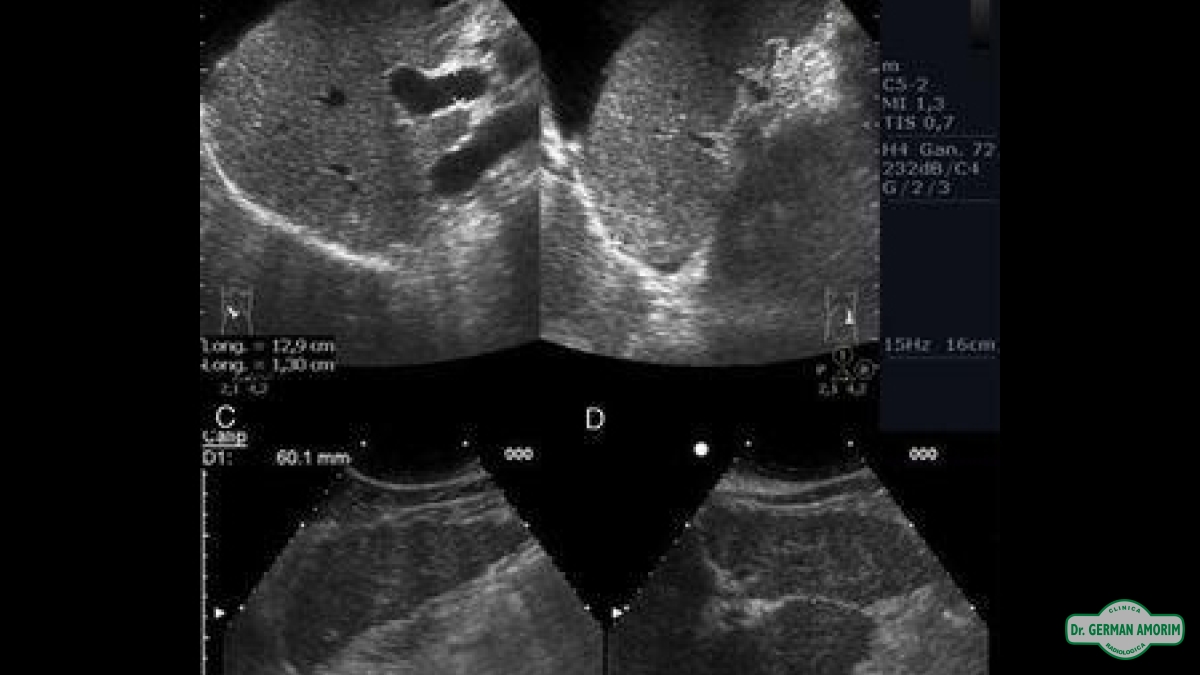

La ecografía o ultrasonografía es un procedimiento de imagenología que emplea ondas de sonido de alta frecuencia dirigidas sobre el cuerpo como fuente de datos, para formar una imagen de los órganos o masas internas con fines de diagnóstico.